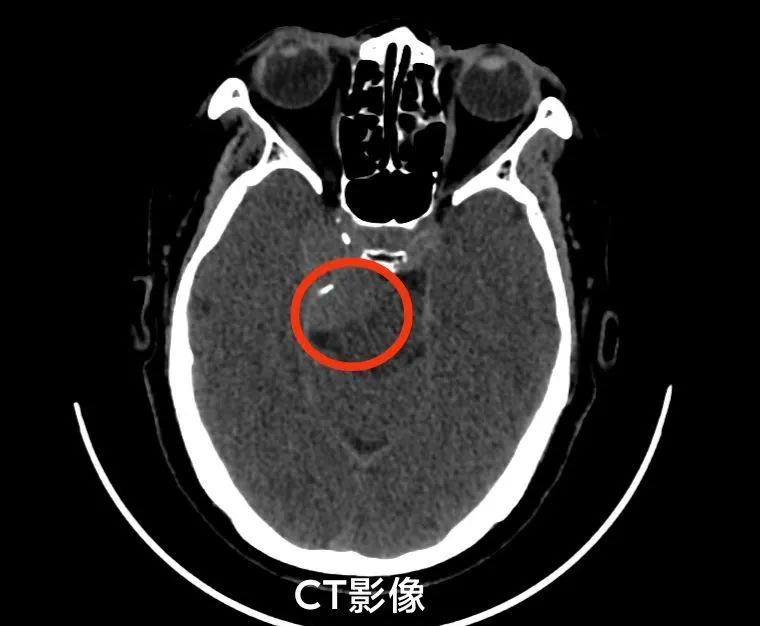

患者柳女士(化姓)半年前出现右侧面瘫,多方治疗后效果甚微。后来到新乡二院进一步检查头颅MRI平扫+增强提示:右侧岩斜区占位,脑膜瘤可能。柳女士辗转找到该院副院长神经外科主任简国庆教授,简院长接诊后发现,柳女士的肿瘤位置很深且紧靠脑干、椎-基底动脉、动眼神经、面听神经、三叉神经等重要结构,手术难度及风险极大。